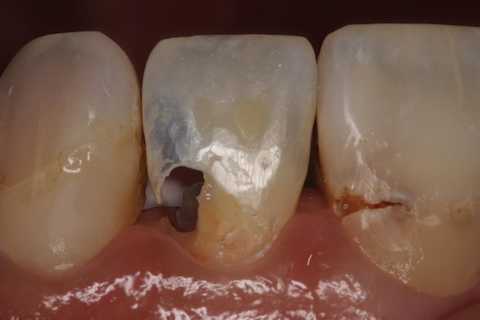

とりあえず健全歯質を確保して、露髄部分は直覆してCRで再建した。

では時系列で、どうぞ